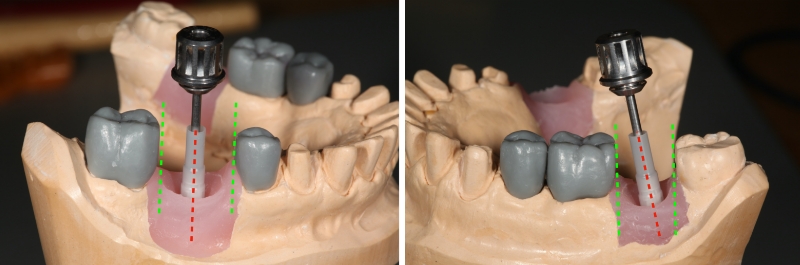

Determining the optimal implant crown placement and angulation can provide the next set of challenges. The more optimal the implant placement and angulation, the fewer insertion challenges. The implant angle relative to the adjacent interdental tooth contours must be considered. Too often, the implant is surgically angulated strictly by evaluation of the adjacent roots rather than considering the angulation of the interproximal tooth surfaces. If the implant is placed off-angle, changing from a straight to an angulated screw access may not solve the insertion path problem.

Most implant abutments extend into the head of the implant by several millimeters to take advantage of the Morris taper and engage in the timing of the “hex”. This insertion angle will dictate whether the interproximal surfaces of the restoration can pass by the interproximal surfaces of the adjacent teeth.

Challenges with the Insertion Path

Additional challenges may be encountered when determining the best insertion path. Solutions can be reached through a possible change to the contour of:

- The adjacent interproximal surface

- The interproximal surface of the restoration.

The negative consequence of altering the implant restoration form interproximally to allow this surface to pass by the adjacent tooth is the opening of the interdental gingival embrasure, which may result in a lateral food impaction area.

There are two things that dictate the insertion path of a screw-retained restoration:

- The angulation of the implant, and

- The interproximal surfaces of the adjacent teeth.